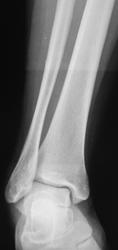

Малый подвывих? стопы (повреждение связок), отрыв заднего отростка таранной кости.

Подвывих в таранно-пяточном суставе и отрыв заднего отростка таранной кости.

В отношении перелома нужно помнить о сверхкомплектной треугольной кости.

Абсолютно согласен с Игорем Ивановичем. а в ЭТОМ случае так тем более...края то заокруглены...

Так и мерещится мне на первых снимках её (внутренней лодыжки) трещина. Думал, что Вы обшиблись/очепятались с наружной-то...

По моему перелом наружной лодыжки накладывается на заднюю, которая цела...